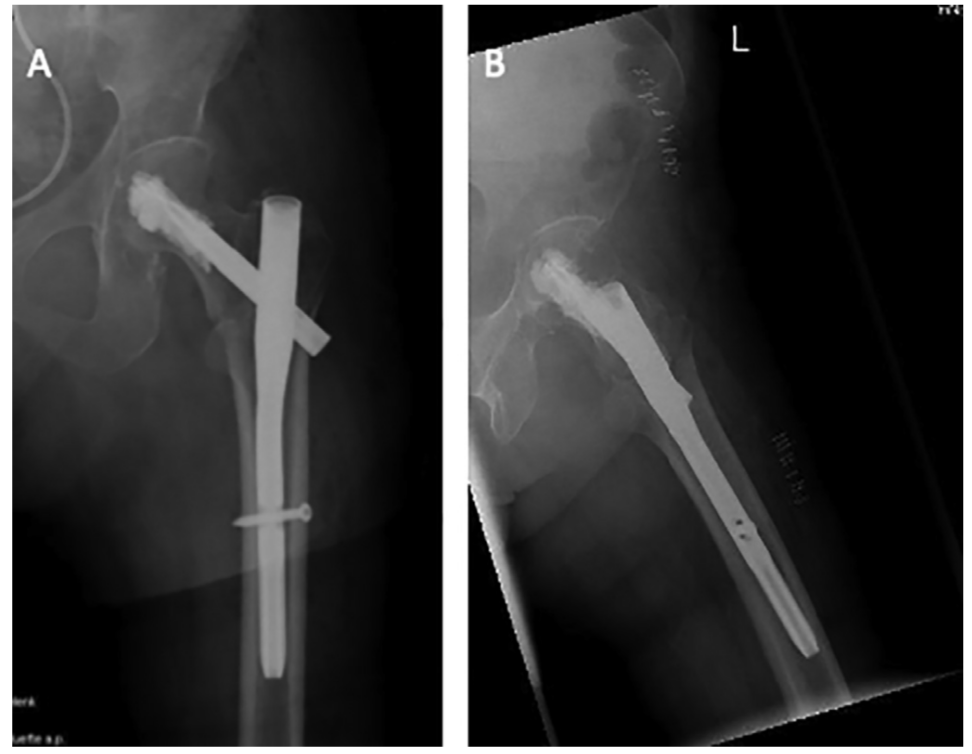

粗隆间骨折髓内固定失效,需要注意这一点!

粗隆间骨折好发于老龄患者,为三大骨质疏松性骨折之一,通常需采用内固定治疗。粗隆间骨折内固定的选择,与骨折类型密切相关。关于小转子及内侧壁的重要性,已经越来越受到重视,部分内固定的失效也与其相关。有学者研究了粗隆间骨折累及小转子及内侧壁的大小与内固定失效的关系,结果发表在Injury期刊上。